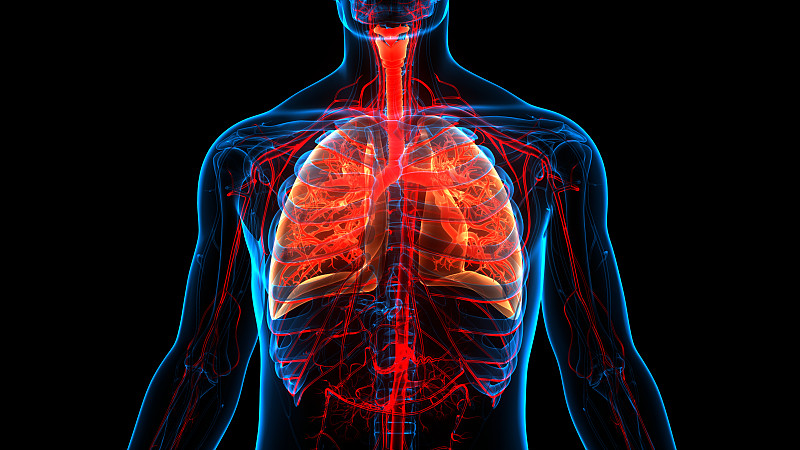

人体呼吸系统肺解剖详情

JPG